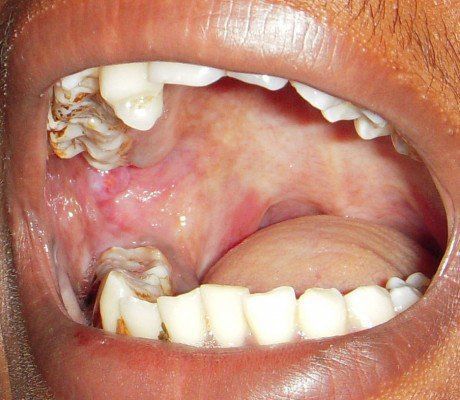

Oral submucous fibrosis is a chronic condition identified as fibrosis of the submucosal tissues of the oral cavity in a progressive manner that leads to restricted mouth opening and eventual inability to open the mouth. This condition results due to chronic chewing of betel quid (main component areca nut that can include pan, gutka, mawa, mainpuri tobacco e.t.c.) and have a well defined potential for malignancy. Text Reference: https://emedicine.medscape.com/article/1077241-overview Image Source: https://www.dovepress.com/oral-submucous-fibrosis-an-update-peer-reviewed-fulltext-article-CCID